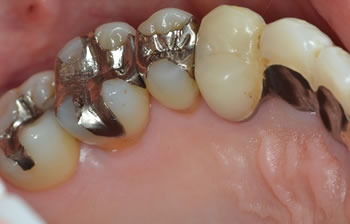

かなり重度の歯周病でグラグラでしたが、仮歯のブリッジで連結固定しまして、歯周外科療法によりエムドゲイン歯周組織再生療法を行いました。

さすがに歯肉退縮はしかたがありませんが、歯肉に炎症もなくメンテナンスされており、今後もこの状態を維持していきたいと思います! |